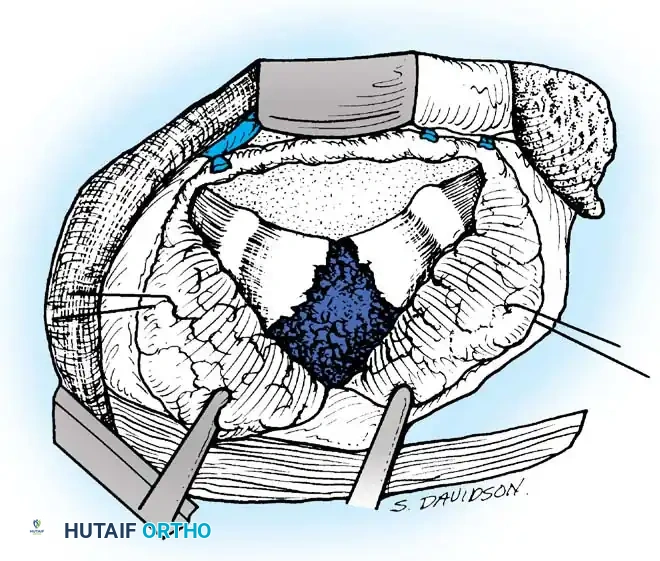

Radical Débridement (Corpectomy)

- Evacuate all liquid pus, caseous debris, and sequestrated bone or disc material using high-powered suction and pituitary rongeurs. If the abscess spans bilaterally, pass the suction tip anterior to the vertebrae into the contralateral cavity to ensure complete evacuation.

- Using osteotomes, high-speed burrs, and rongeurs, radically excise all diseased, sclerotic, and necrotic bone.

- The excision must extend posteriorly to the posterior longitudinal ligament (PLL). Remove the PLL and any tuberculous granulation tissue to fully decompress the ventral dura.

- Crucial Step: Excise the entire affected vertebral body. Tuberculous collections and sequestrated disc fragments frequently hide in the spinal canal posterior to seemingly intact posterior vertebral body walls.

- Remove the intervertebral discs at the cranial and caudal extents of the cavity until normal, bleeding endplates are exposed.